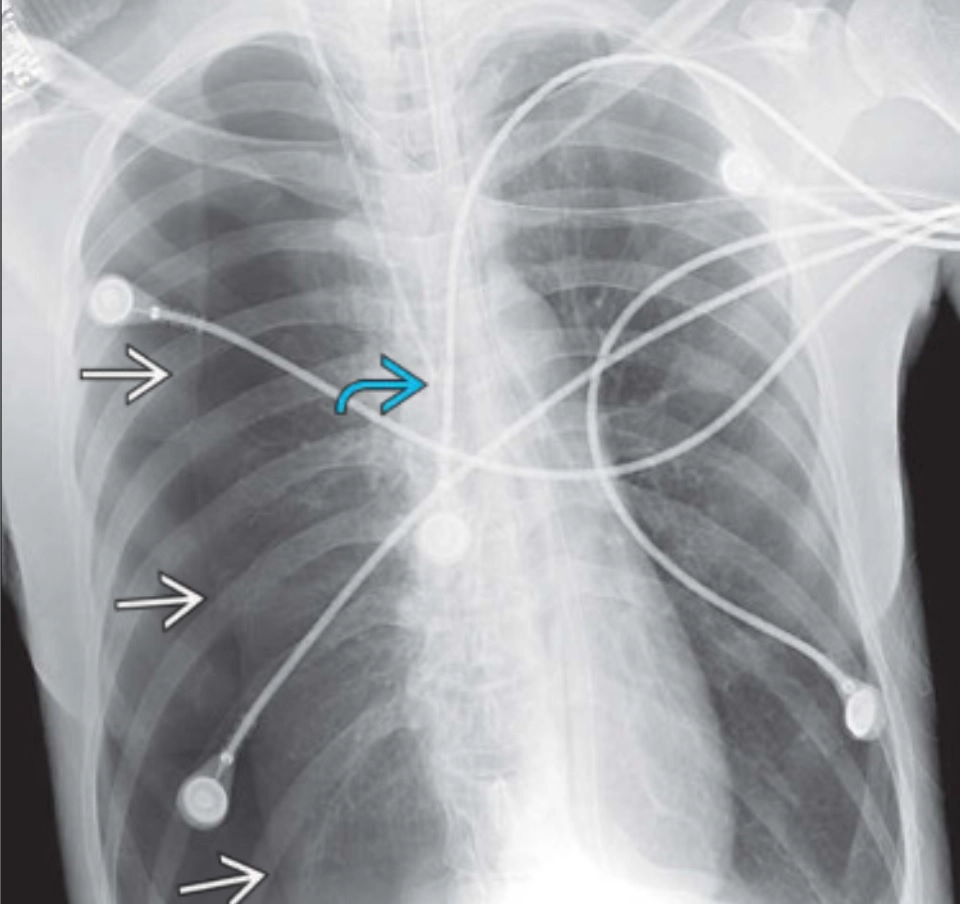

Hình ảnh ICU và thiết bị hỗ trợ (ICU imaging & support devices)

16/03/2026